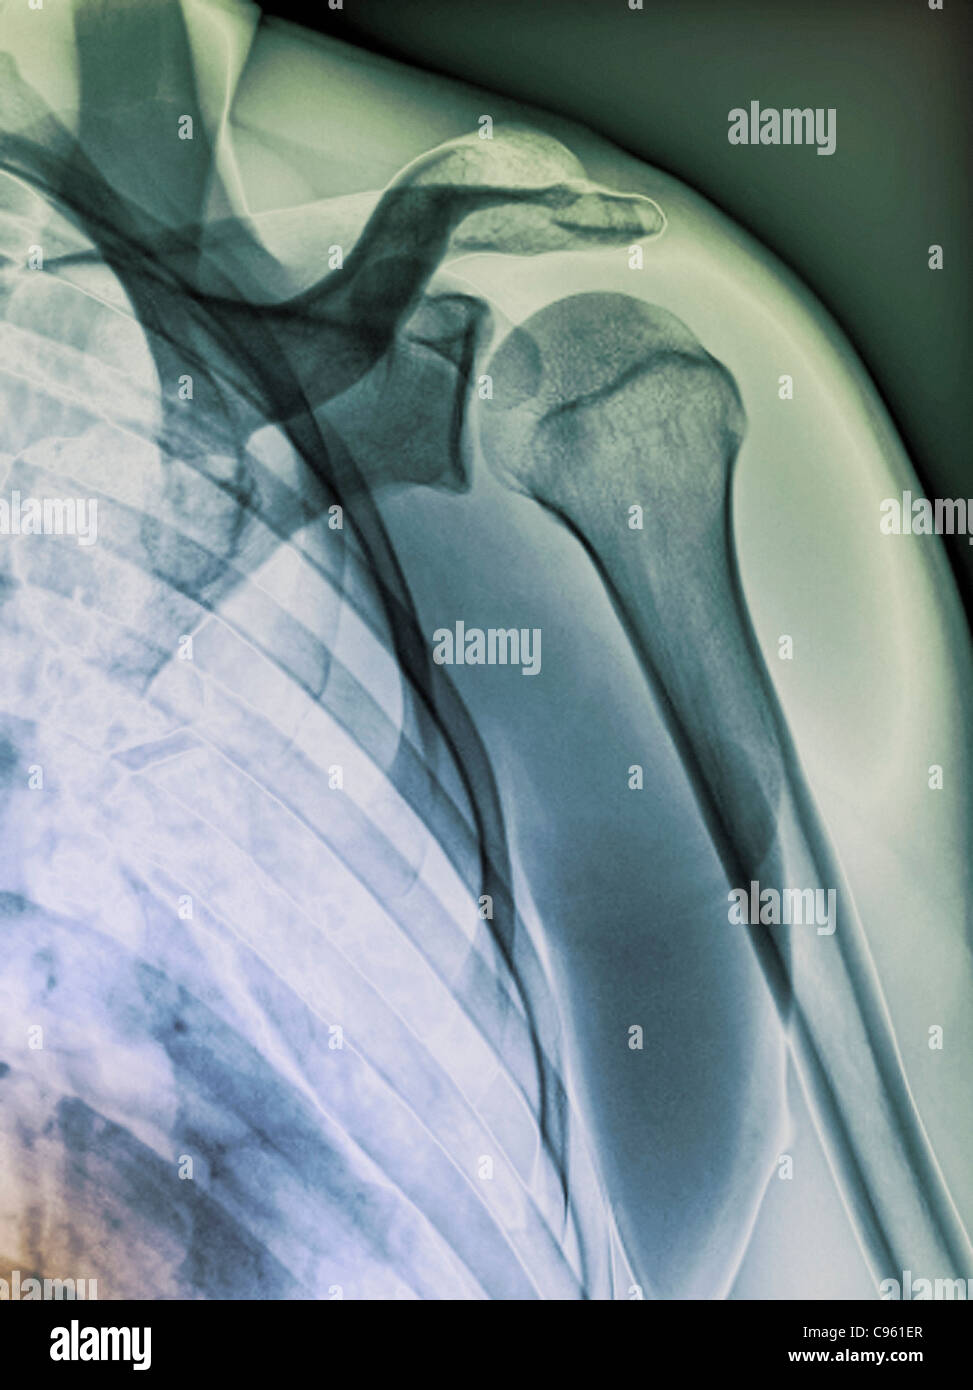

Normal shoulder. Coloured Xray of the healthy left shoulder of a 28 year old patient Stock Shoulder X Ray Healthy Stress, among other things, can make your shoulder muscles quite cranky. Soft tissue areas, cortical margins, trabecular patterns,bony. A recommended systematic checklist for reviewing musculoskeletal exams is: A normal shoulder x ray will demonstrate the bones of the shoulder to have expected normal appearance without breaks, bone. Ideally, a shoulder radiograph series will provide adequate views of the clavicle, acromioclavicular. Shoulder X Ray Healthy.